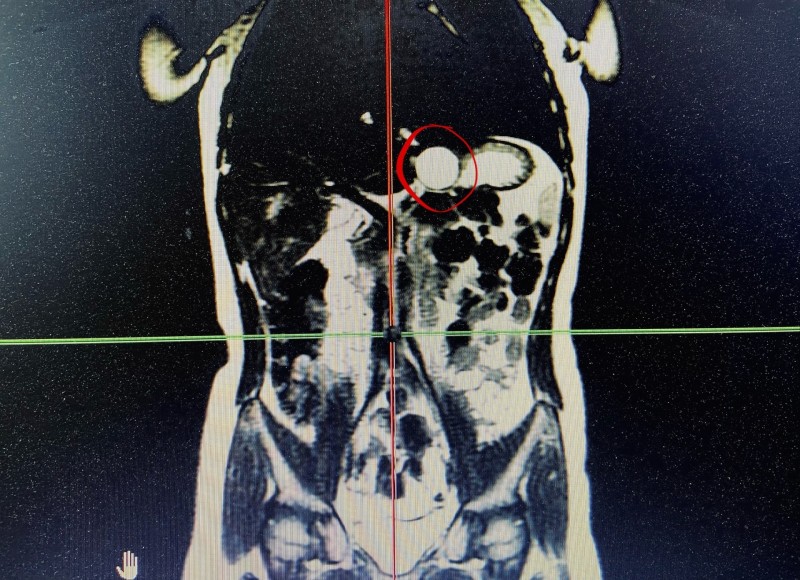

Кистозное удвоение желудка – врожденная аномалия развития желудочно-кишечного тракта, при которой формируется отдельная полость, не связанная с просветом основного желудка. После детального обследования с применением компьютерной томографии специалисты Республиканской детской клинической больницы установили показания к удалению образования.

"Кистозное удвоение в диаметре около трех сантиметров располагалось в области перехода кардиального отдела желудка в пищевод, – рассказал главный детский хирург Минздрава Коми, заместитель главного врача по хирургии РДКБ Руслан Ислентьев. – Неудаленное образование грозило воспалением и нагноением в брюшине".